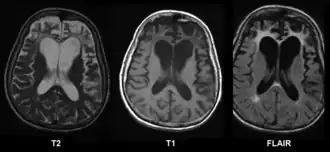

![]() Resonancia magnética cerebral en un caso de Enfermedad de Pick | ||